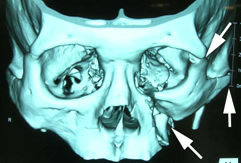

頬骨は頬(ほお)部に突出した骨で、頬に加わった力により骨折を来します。症状としては頬部の平坦化、眼球運動障害による複視(物が二重に見える)、頬部の知覚障害(ほおやくちびるのしびれ)、開口障害(口が開きにくい)などがみられます。治療は偏位した頬骨の整復と固定が原則で、眉毛外側、下眼瞼縁および必要に応じて口腔内に皮膚切開を加えて骨折部を露出し、直視下に整復してプレートで固定するのが一般的です。当科では、骨折の状態や症状によって、手術中に超音波診断装置を用いて整復の状況(治り具合)を評価して固定する手術方法を行っています。この方法では、皮膚の切開を眉毛外側の小さな切開のみに限定することができます。固定は、眉毛部の1箇所のプレート固定とワイヤーによる固定を行います。ワイヤーは、術後6週間程度で外来にて5分程度で抜去します。顔面のキズと骨の周囲の剥離(手術の操作)を最小限にするため低侵襲(体に負担の少ない)であり、術後の腫れが少なく、入院期間も短縮できる手術方法です。

![]() |

また、骨折の状態によって、眼窩骨骨折と同様に3Dモデルを作成するシミュレーションサージャリーを行っています。 |

| 頬骨骨折3次元CT像 |